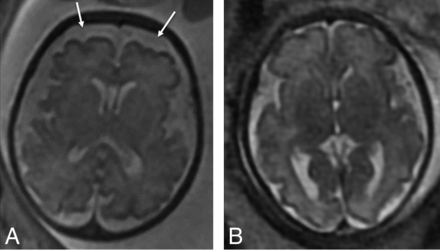

On fetal MR imaging, enlarged extra-axial spaces were the most common brain finding, seen in 22/36 MRIs (Fig 2). Other less common findings were the presence of venous sinus distention (Fig 3) and ventriculomegaly (Table 2). Ventriculomegaly was mild, seen only on the early MR imaging in 2 infants and resolved on the subsequent third trimester MR imaging. There were no cases of maturational delay, intracranial hemorrhage, or brain parenchymal injury identified on fetal MR imaging. Findings related to CDH severity are listed in Table 3.

Axial T2-weighted images of two 32-week fetuses with CDH with enlarged extra-axial spaces as marked by arrows (A) and normal extra-axial spaces (B).

Coronal T2-weighted images of a 34-week fetus with CDH (A) with engorged dural venous sinuses (arrows) and a comparison 34-week fetus without CDH (B) without dural venous sinus engorgement.